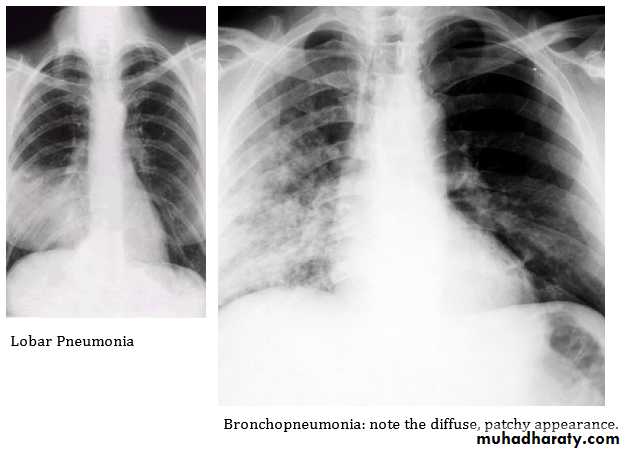

2- Morphology: Bronchopneumonia vs. lobar pneumonia (which may be segmental, lobar or multilobar).

Lobar pneumonia: is a radiological and pathological term referring to homogeneous consolidation of one or more lung lobes, often associated pleural inflammation.

Bronchopneumonia: refers to more patchy alveolar consolidation associated with bronchial and bronchiolar inflammation often affecting both lower lobes

• Lobar pneumonia: Patchy opacification evolves into homogeneous consolidation of affected lobe. Air bronchogram (air-filled bronchi appear lucent against consolidated lung tissue) may be present

• Bronchopneumonia: Typically patchy and segmental shadowing

Lobar pneumonia

PA chest x-ray shows consolidation in the left lung base. A lateral view was obtained and shows that the consolidation is located posteriorly. Lateral view are especially important in showing infiltrates, which may be obscured by the heart on PA view.